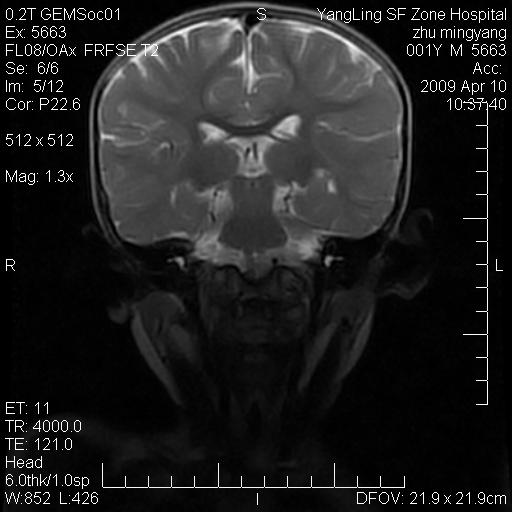

患者:1岁半,两天前外伤收住我院,ct检查小脑占位

考虑星形细胞瘤,建议增强

髓母细胞瘤或血管母细胞瘤,增强后可以鉴别;影像资料见 <。鱼博浪老师的《中枢神经系统ct与mr鉴别诊断》 小脑部肿瘤章节。

髓母细胞瘤或血管母细胞瘤!支持!

支持考虑髓母细胞瘤

考虑----髓母细胞瘤可能性大

考虑髓母细胞瘤或室管膜瘤。

支持髓母细胞瘤。

考虑髓母细胞瘤。

考虑髓母细胞瘤或星形细胞瘤

考虑髓母细胞瘤.

考虑髓母细胞瘤可能性大。

小脑肿瘤.考虑髓母细胞瘤可能.

就病灶部位及临床资料首先考虑髓母.